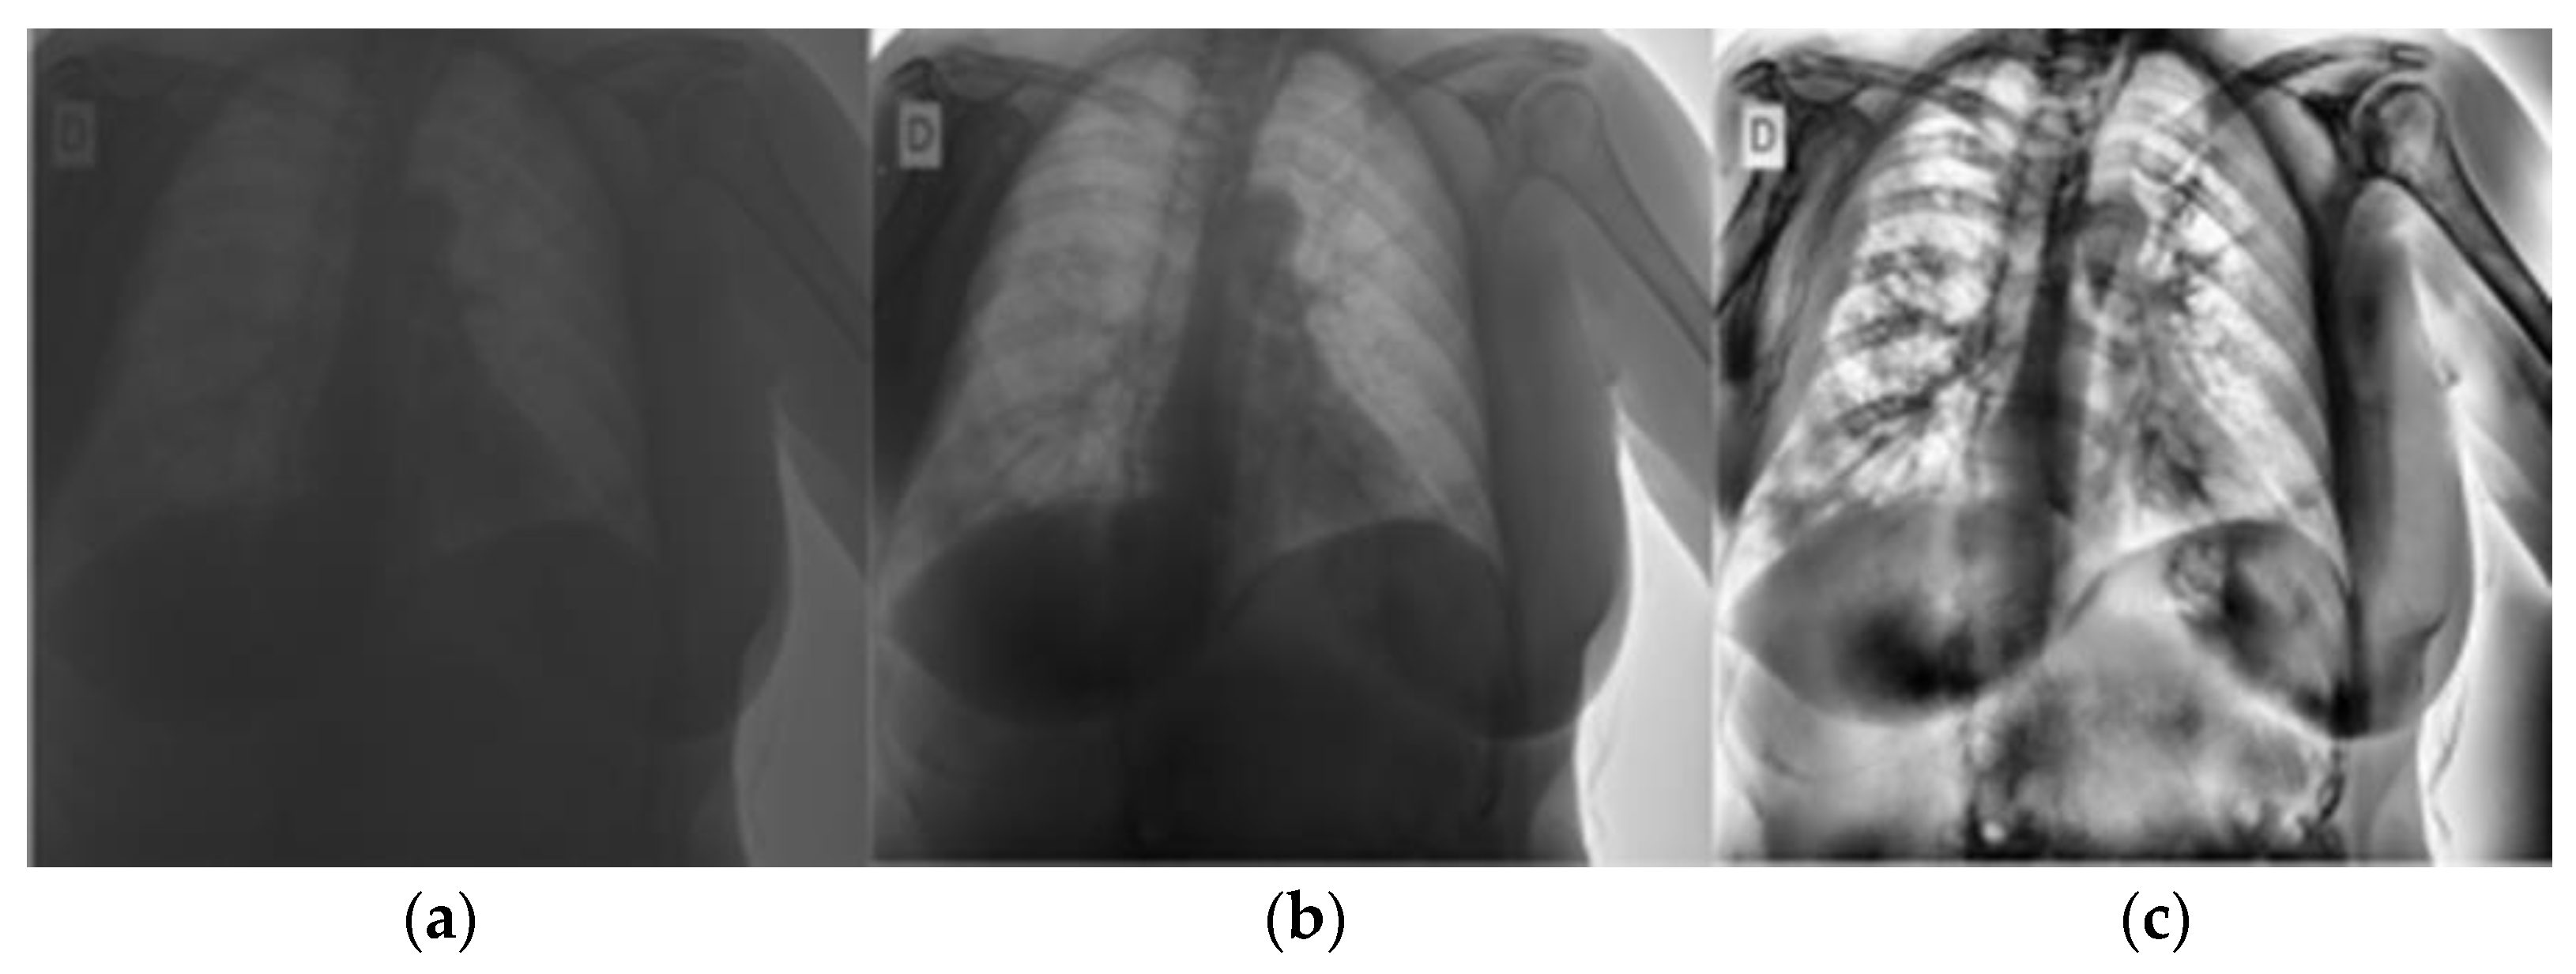

Local contrast and edges were made more visible using computer limited adaptive histogram equalization (CLAHE). This allowed COVID-19 symptoms to be visible in the lungs []. CLAHE is a version of adaptive histogram equalization (AHE). In AHE, the image is divided into tiles, and each tile has its contrast enhanced by considering the pixels in the tile. However, AHE tends to over-amplify noise in nearly uniform image regions. CLAHE overcomes this by limiting amplification []. The transformation of images using CLAHE is shown in Figure 4.

Figure 4.

Pre-processing applied to CXRs. (a) Original image, (b) Pixel re-scaled image (c) Image after CLAHE.